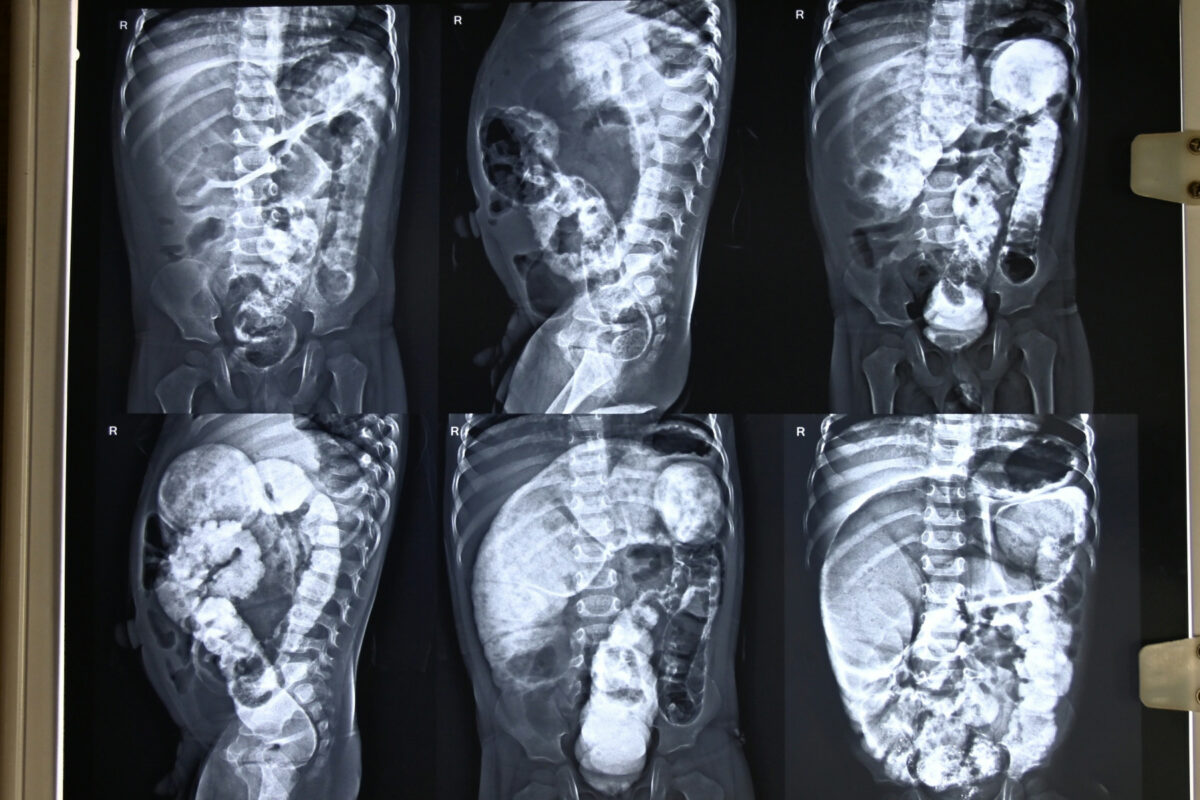

In desperation, the worried parents rushed to Hallet Hospital, Kanpur, where after a series of investigations, including a Barium Enema X-ray, their worst fears came true —

the child was diagnosed with Hirschsprung’s Disease (Congenital Megacolon), a condition where part of the intestine lacks nerve cells, making it unable to pass stool naturally.